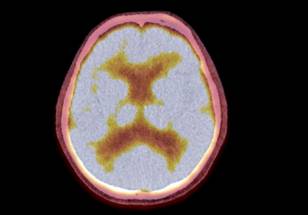

“What we like about the AMPET is that it moves with the head, and you can be in a real environment where you’re immersed and walk with it on,” she said. “What we demonstrated in the study is that when the patients walk, it’s not moving relative to the head and that’s what allowed us to get a relatively clean image. We also wanted to see what should be improved by us or other laboratories that are making these devices.”

“We observed brain activity in the parts of the brain that control leg movements when the patients walked, which was what we had hoped to see,” Brefczynski-Lewis said.